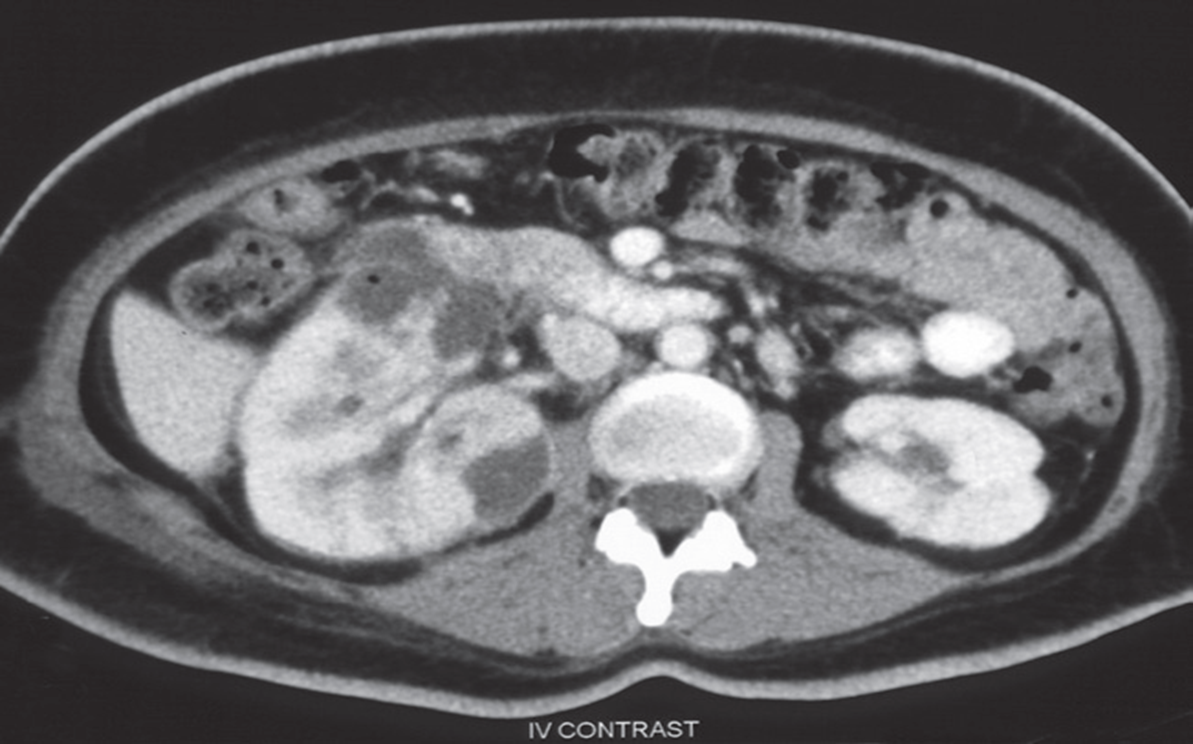

\CT scan with intravenous contrast demonstrating multiple low attenuation fluid collections in the right renal cortex, consistent with multiple renal abscesses.

An abscess appears as a well-defined mass of low attenuation with a thick, irregular wall or pseudo capsule, which can be better visualized on contrast enhanced scans CECT.

Gas within a low attenuation/cystic mass strongly suggests abscess formation.